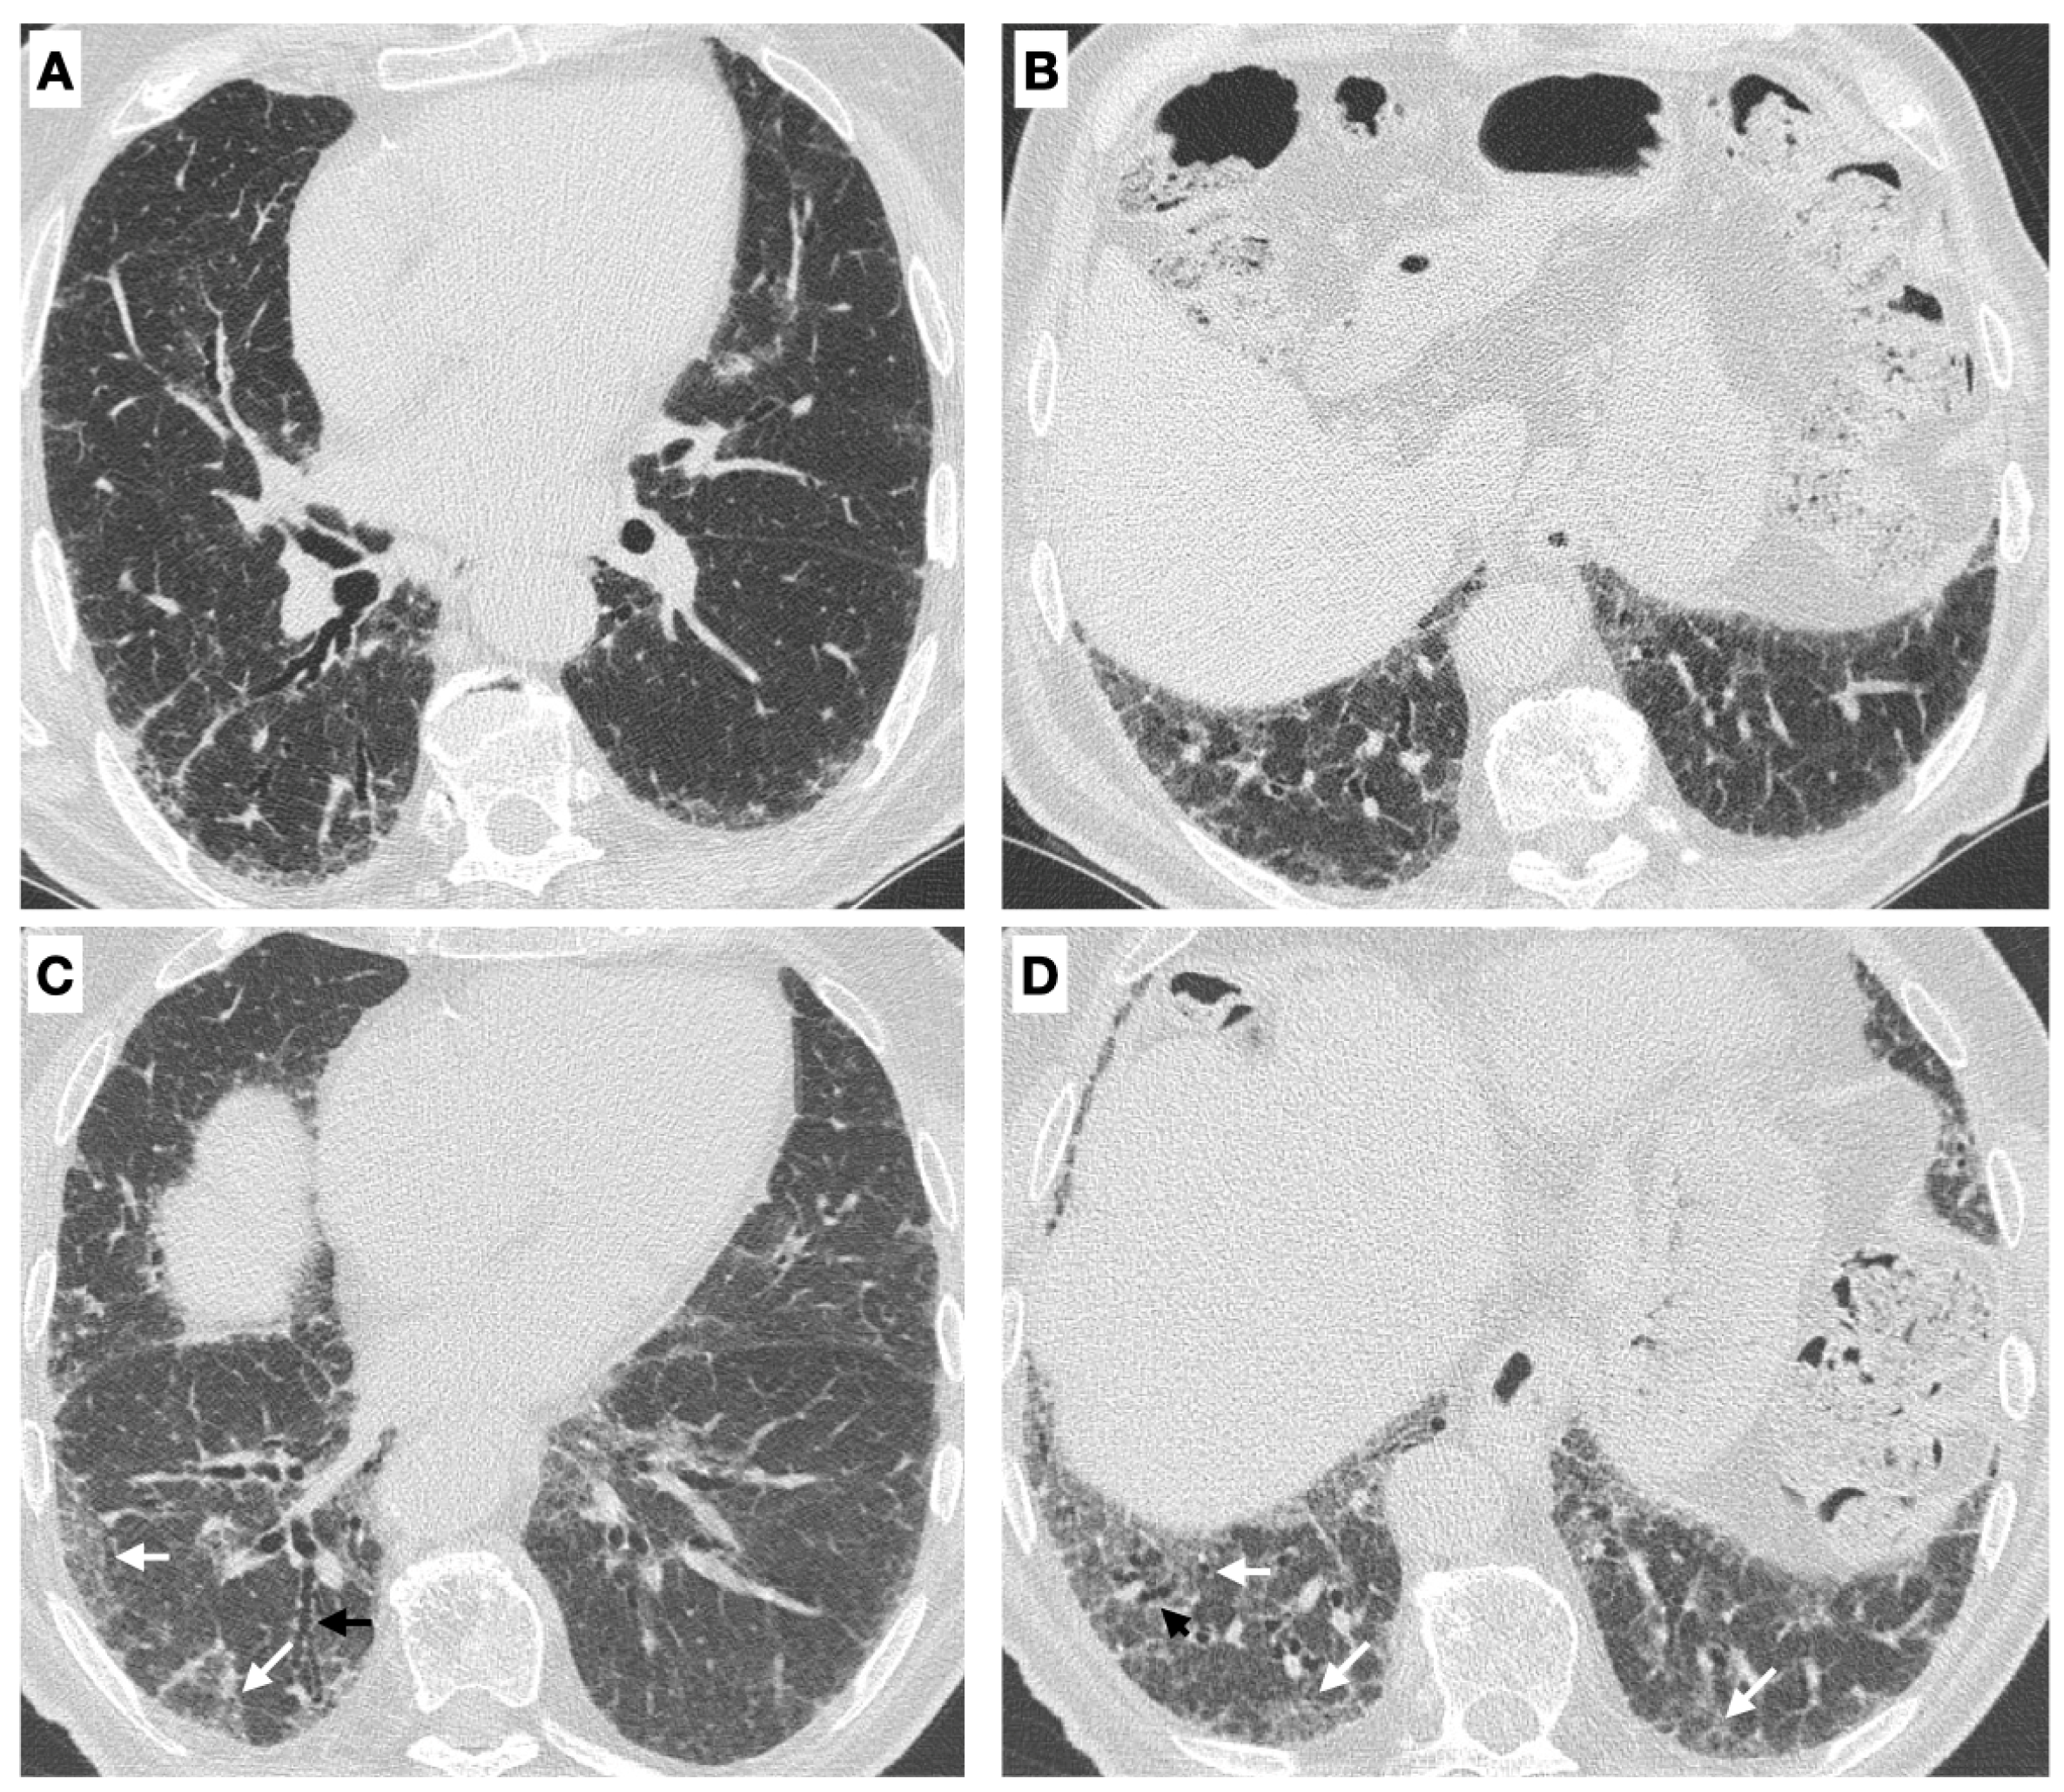

- Radiological progression on HRCT: the trend of ILD (stable, deteriorated, or ameliorated) was established by the most expert thoracic radiologist, blinded to the clinical and functional evaluation, through a semi-quantitative analysis. Particularly evaluated were the presence or increase of the extent of traction bronchiectasis/bronchiolectasis, ground glass opacities, reticulation, and honeycombing as well as the increase of the lobar volume loss [31]. Figure 2 reports an example of ILD progression on HRCT.